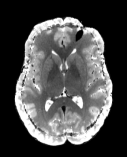

Reversed Gradient Polarity (RGP) methods are commonly used to correct susceptibility artifacts in Echo-Planar Imaging (EPI) [Stehling et al., 1991]. RGP methods acquire a pair of images with opposite phase encoding directions, which leads to a minimal increase in scan time due to the speed of EPI. In a post-processing step, RGP approaches use the fact that the distortion in both images has an equal magnitude but acts in opposite directions to estimate the field map (see Figure 1) [Chang and Fitzpatrick, 1992, Bowtell et al., 1994]. The field map is then used to estimate a distortion-free image.

Refer to captionRefer to captioninput images+v𝑣+vv𝑣-vRefer to captionoptimizeRefer to captionfield map b𝑏bRefer to captionapply modelRefer to captioncorrected image \mathcal{I}

Figure 1: The Reverse Gradient Polarity correction paradigm. Two images are acquired with opposite phase encoding directions, +v𝑣+v and v𝑣-v. These two images are used to estimate the field map b𝑏b, and the distortion correction model [Chang and Fitzpatrick, 1992] is applied to obtain a corrected image \mathcal{I}.